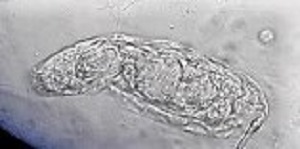

A 10-year-old female patient from Argentina was taken to the hospital by her parent with complaints of “not feeling well.” A urine sample was collected and examined as part of the routine checkup. Microscopic examination of the urine sediment using the 40x objective lens revealed the following: 0-1 WBC and 0-2 RBC per field and a motile organism shown in the video that was sent to the DPDx team for identification. Still images of the organism were made by capturing screenshots at different points of the video (Figures A – C). What is your diagnosis? Based on what criteria?

Figure A